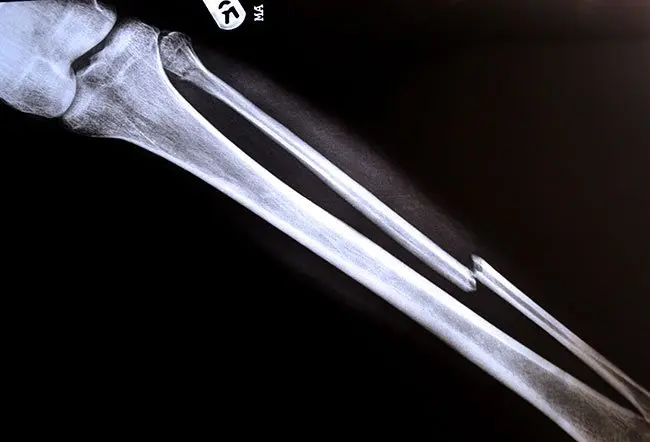

Molti muscoli della coscia e della gamba si inseriscono sulla fibula attraverso i tendini. Questo osso viene anche talvolta utilizzato per trapianti ossei in altre parti del corpo, vista la sua importanza come “fonte” di tessuto osseo. In caso di lesioni, come le fratture, il tempo di guarigione della fibula è generalmente compreso tra tre e sei mesi. Questo periodo può variare in base a diversi fattori, tra cui l’età del paziente, i livelli di vitamina D nel sangue e la tipologia di frattura. Il processo di recupero può essere favorito da un adeguato riposo, dall’evitare di caricare eccessivamente la gamba lesionata e dal rispetto scrupoloso delle indicazioni mediche.

L’osso fibulare si estende dall’articolazione del ginocchio fino a quella della caviglia. La sua parte superiore, detta testa della fibula, si trova appena dietro la testa tibiale, vicino al ginocchio. Scendendo verso il basso, si distingue il collo seguito dalla diafisi, ovvero il corpo dell’osso. La forma della diafisi è determinata dagli attacchi muscolari che vi si inseriscono. L’estremità distale della fibula contribuisce a formare la cosiddetta “malleolo laterale”, la prominenza ossea visibile e palpabile sul lato esterno della caviglia. Questa estremità mantiene un contatto articolare con le ossa del piede, garantendo mobilità e stabilità della caviglia stessa. La fibula è connessa alla tibia tramite una membrana interossea, una sottile lamina di tessuto fibroso che corre lungo la superficie mediale dell’osso.